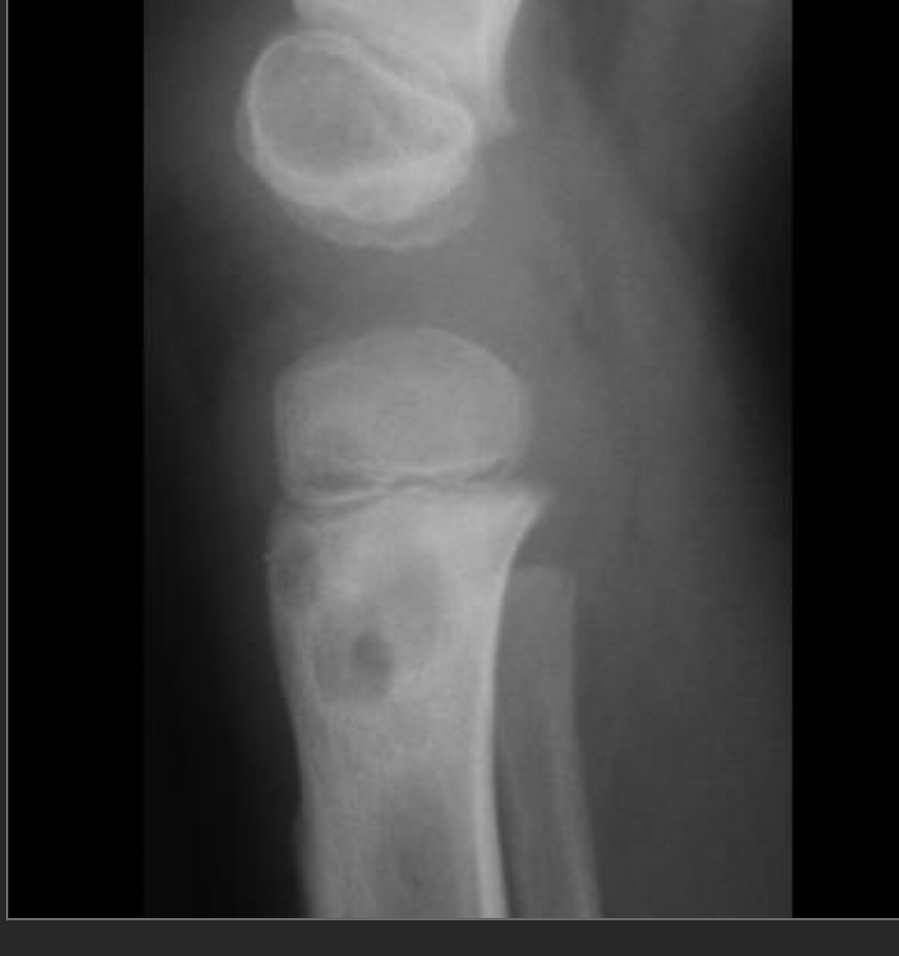

2.5 year old boy who won’t bear weight

Osteomyelitis

typical appearance and location for osteomyelitis.

Extension into the epiphysis is typical; may be seen with tumors but more common with osteomyelitis.

The diffuse sclerosis surrounding the lytic lesions represents typical host reaction to the infection.